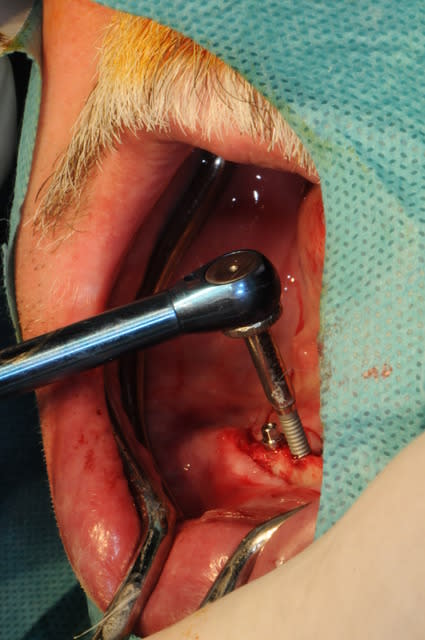

Bon, je viens de lui poser ses 4 mini-implants ce matin.(diamètre2.8 longueur 13mm)

non, c'était juste pour la photo et montrer qu'on pouvait poser à la main (dure dure), au CA et avec la clé...

la photo 8 donne l'impression d'un axe en direction linguale certainement trompeuse.

tu n'as pas de téléradio de profil ?